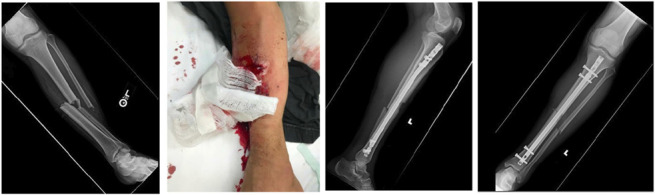

Tibial shaft fractures are one of the most common orthopaedic injuries. Open tibial shaft fractures are relatively common because of the paucity of soft tissue surrounding the bone. Despite the prevalence of these injuries, the optimal fixation strategy is still a topic of debate. The purpose of this article was to review the current literature on open tibial shaft fracture fixation strategies including intramedullary nailing, external fixation, and plating.

Abstract Image